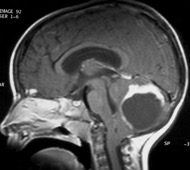

l’hydrocéphalie tumorale

est due à un blocage de la circulation du liquide cérébro-spinal, c’est l’hydrocéphalie tumorale, fréquente dans les tumeurs intraventriculaires et les tumeurs de la fosse postérieure.